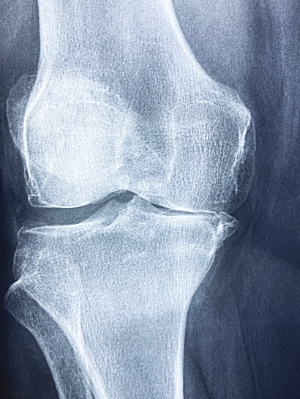

6. 퇴행성 관절염

퇴행성 관절염은 나이가 들어가면서 뼈, 인대, 근육 등의 조직이 퇴행하고 연골이 점차적으로 닳아서 염증이 발생하여 통증을 유발하는 상태를 말합니다. 주로 노년층에서 발생하는 이 질환은 노화와 밀접한 관련이 있습니다. 대부분 무릎에서 증상이 나타나지만, 어깨, 손가락, 척추 등 다른 관절 부위에서도 발생할 수 있어 항상 주의해야 합니다.